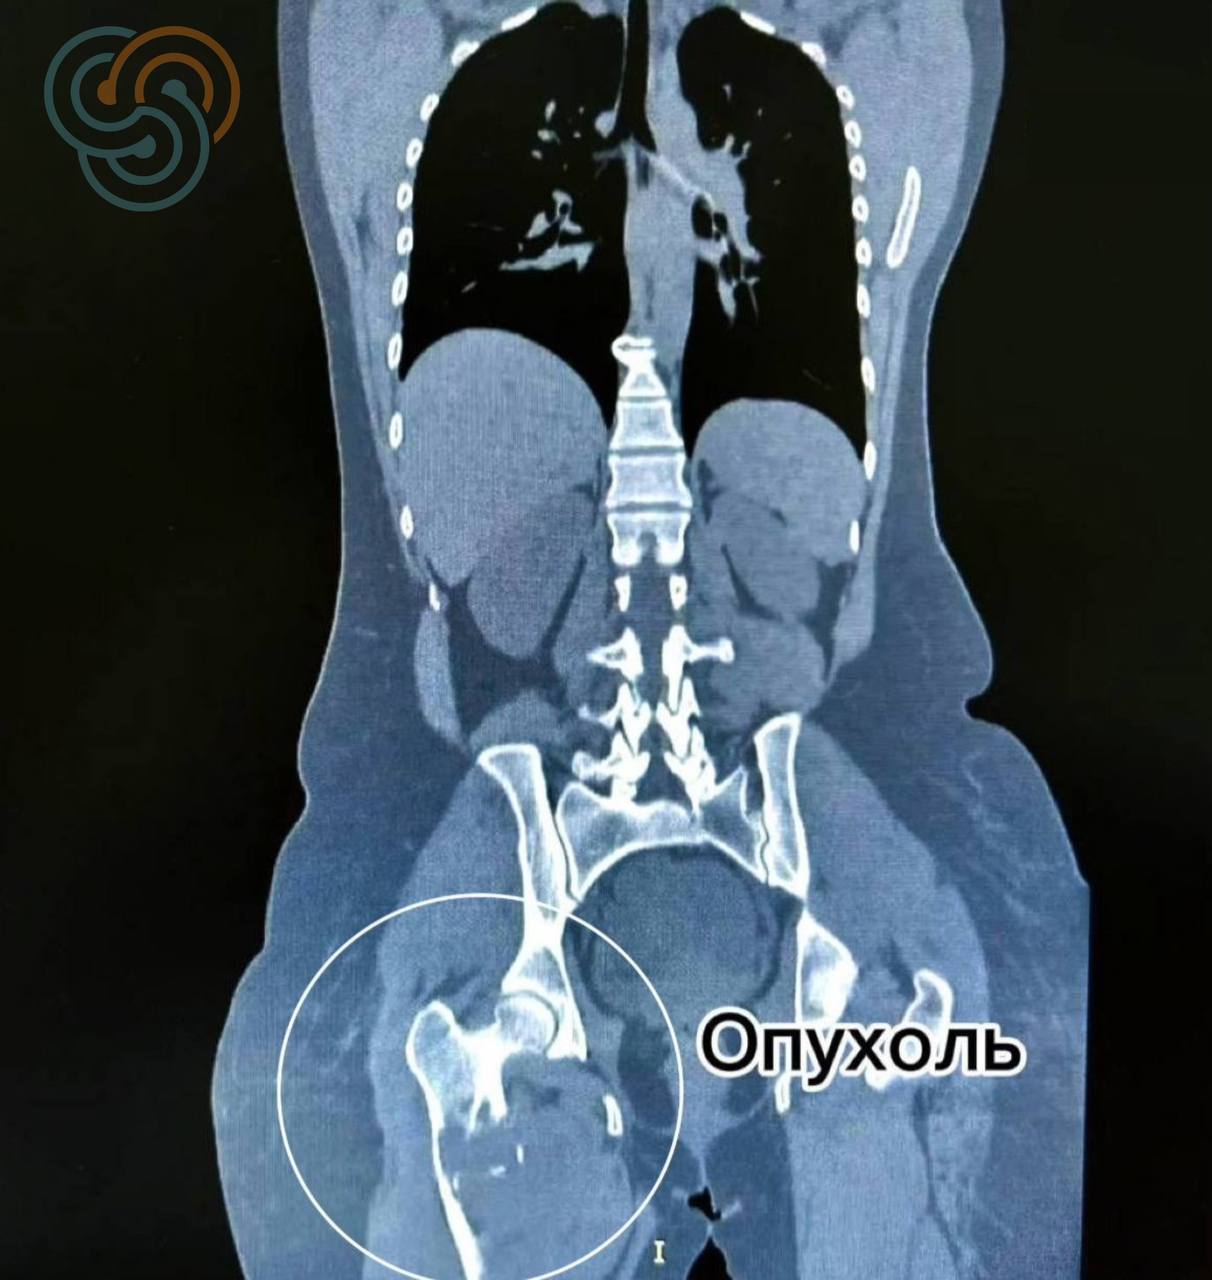

Биопсия материалын федераль үзәккә диагнозны ачыклау өчен җибәргән арада авыру көтеп тормаган. Шеш бот сөяген җимерә, һәм тиздән иң авыр катлаулануларның берсе — патологик сыну барлыкка килә.

Мондый ситуацияләрдә медицина тактикасы күпчелек очракта ампутацияне күздә тота – процессны туктатырга мөмкинлек бирә торган карар, ләкин пациентның тормыш сыйфатына җитди йогынты ясый.

Декабрьдә Татарстанда моңа кадәр үткәрелмәгән операция ясалды: янбаш һәм тез буыннарына тоталь эндопротез ясап, зарарланган бот сөяген тулысынча алыштыру.